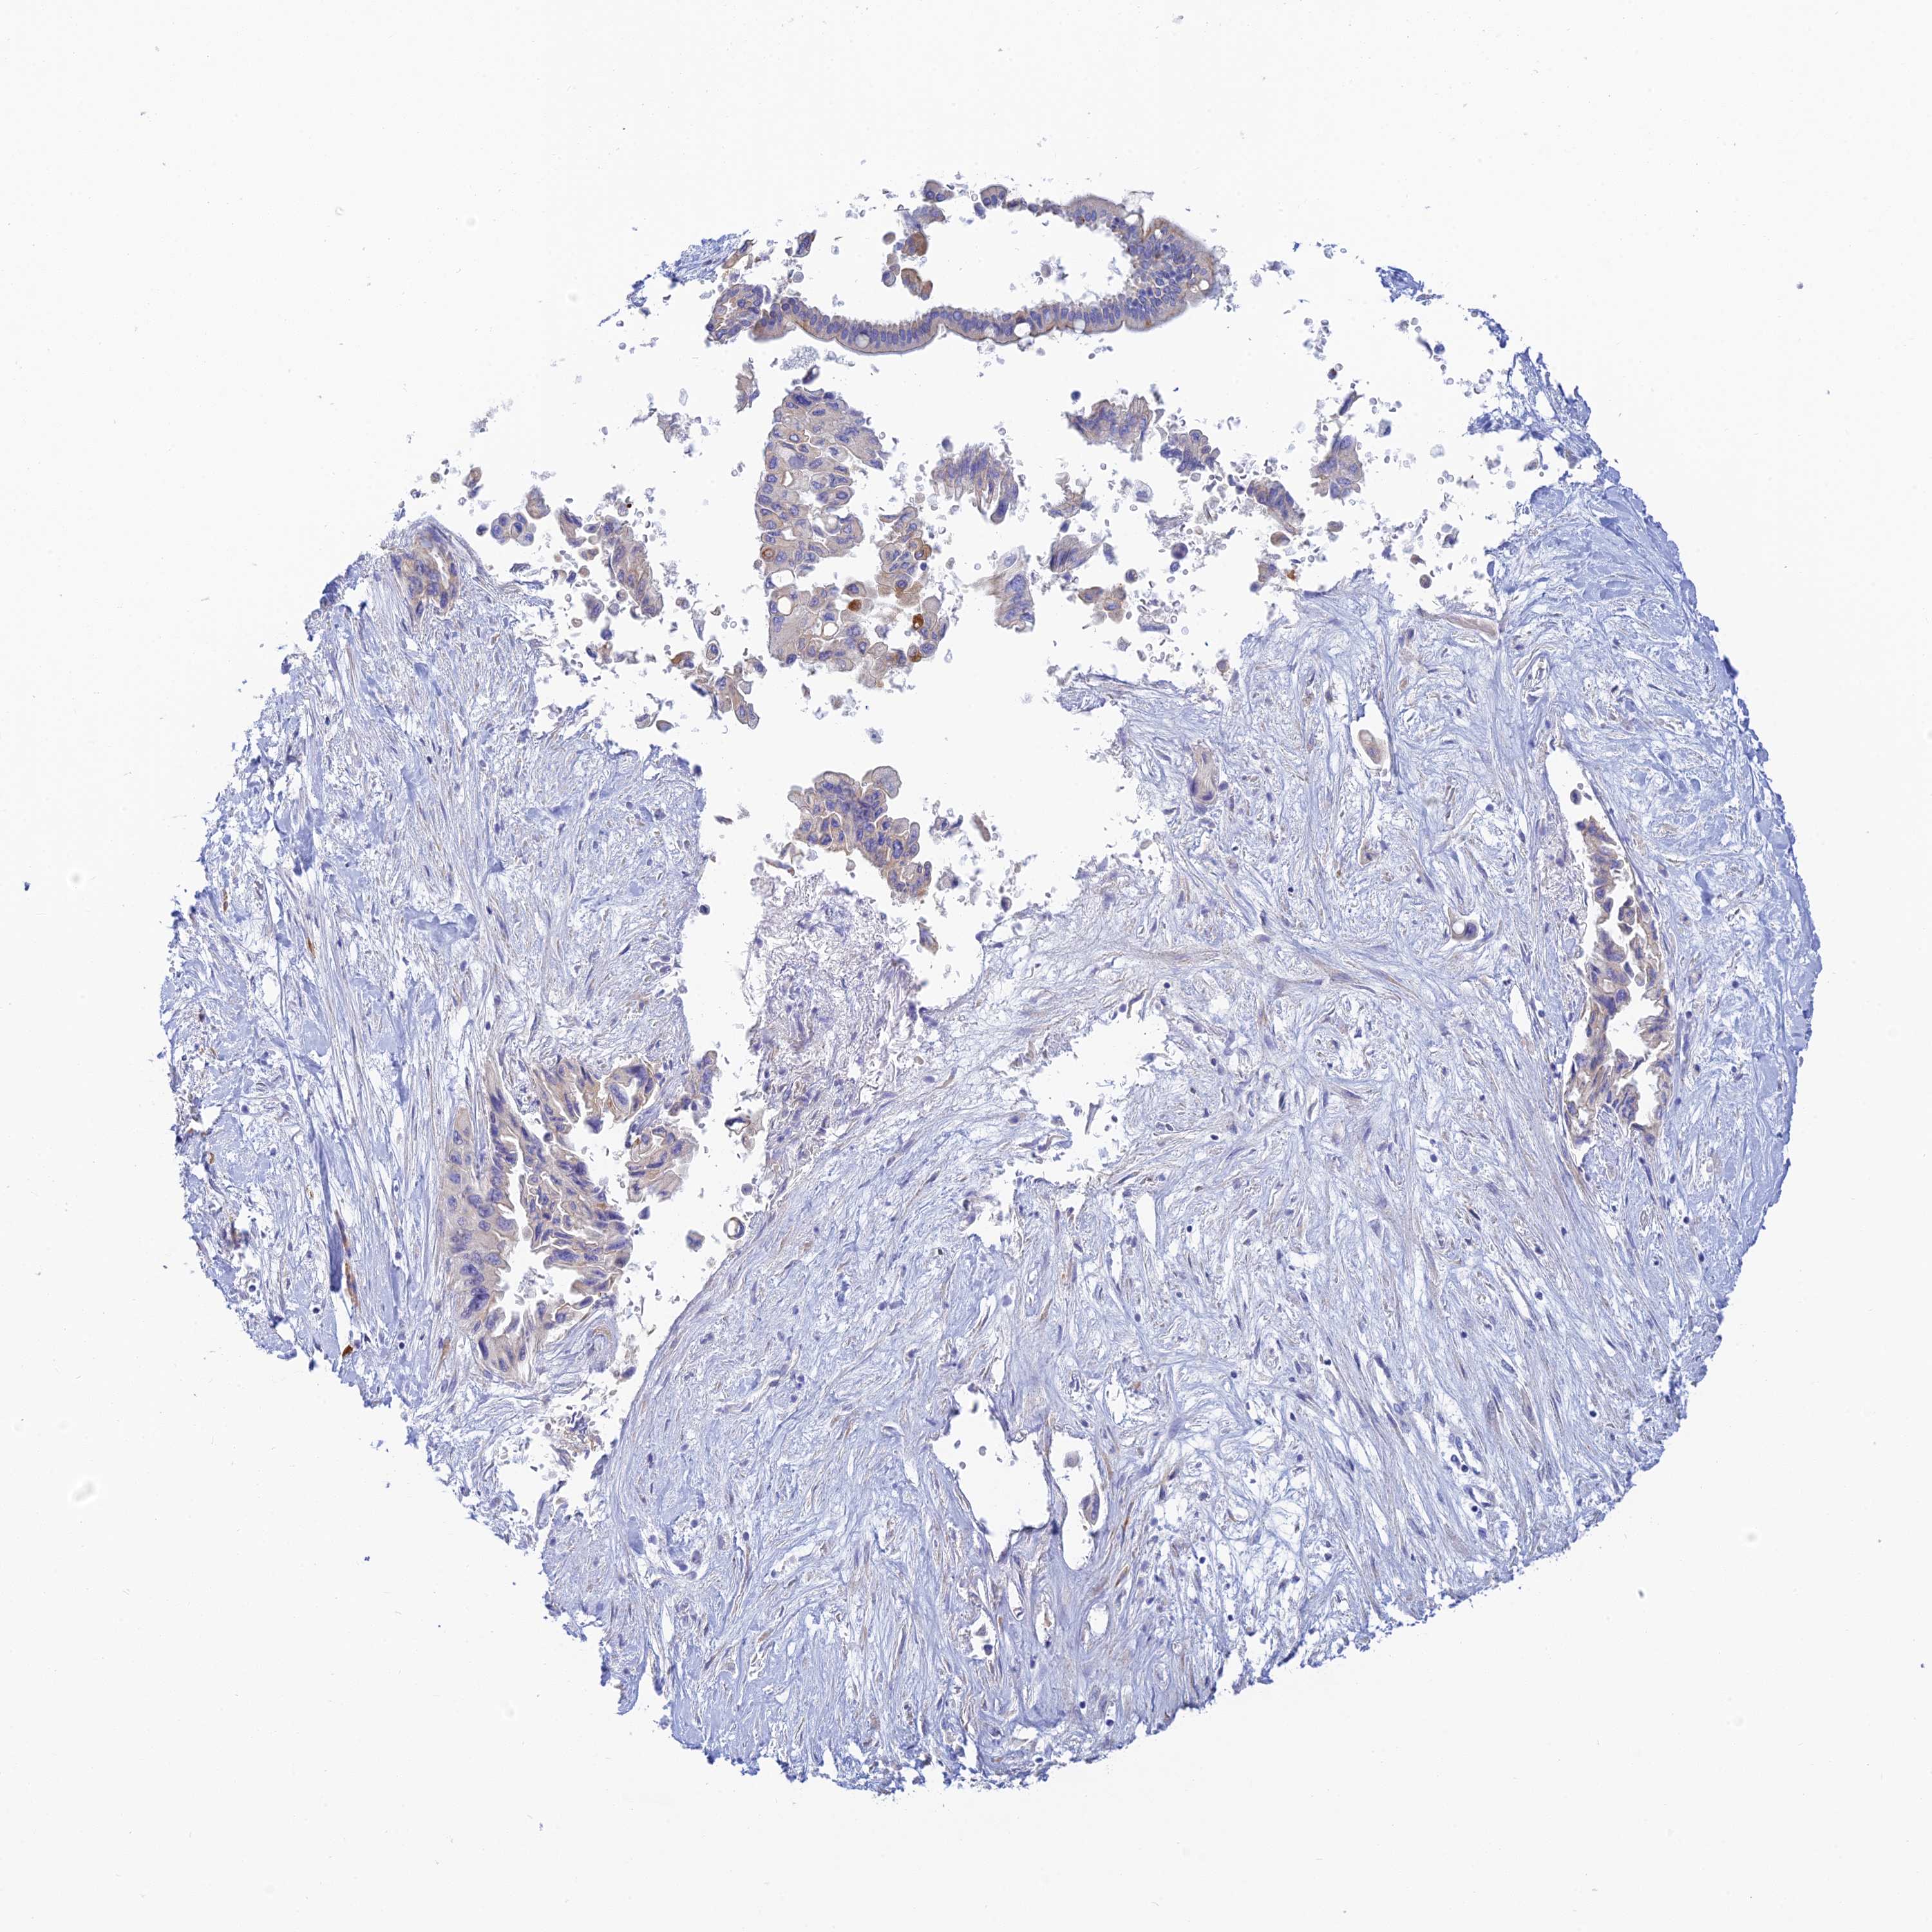

PANCREATIC CANCER - Protein expressioni

A mouse-over function shows sample information and annotation data. Click on an image to view it in a full screen mode. Samples can be filtered based on level of antibody staining by selecting one or several of the following categories: high, medium, low and not detected. The assay and annotation is described here.

Note that samples used for immunohistochemistry by the Human Protein Atlas do not correspond to samples in the TCGA dataset.

Antibody stainingi

Antibody staining in the annotated cell types in the current human tissue is reported as not detected, low, medium, or high, based on conventional immunohistochemistry profiling in selected tissues. This score is based on the combination of the staining intensity and fraction of stained cells.

Each image is clickable and will lead to virtual microscopy that enables deeper exploration of all samples and also displays staining intensity scores, fraction scores and subcellular localization as well as patient and tissue information for each sample.

Antibody HPA039408

Staining

High

Medium

Low

Not detected

Intensity

Strong

Moderate

Weak

Negative

Quantity

>75%

75%-25%

<25%

None

Location

Nuclear

Cytoplasmic/membranous

Cytoplasmic/membranous,nuclear

Adenocarcinoma, NOS